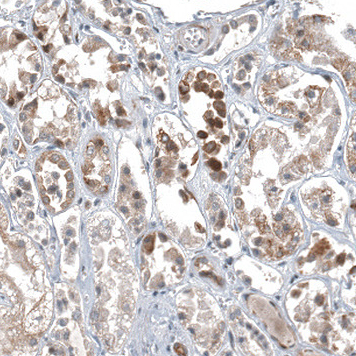

Immunohistochemical staining of human testis shows moderate nuclear positivity in cells in seminiferous ducts.